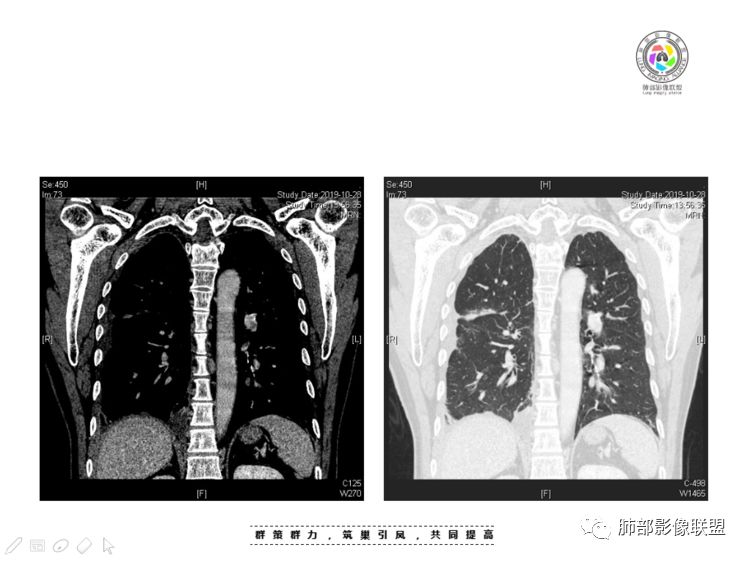

穿越七海的风:右前纵隔占位,恶性肿瘤,生殖来源?右肺实变是占位or肺不张?考虑为部分肺不张FeNo:右前纵隔占位,右肺结节,胸膜凹陷,小尾巴,右肺不张,考虑恶性杨旭华:恶性,前纵隔肿物,与血管关系密切,上腔静脉变窄,右肺野一元论考虑叶间裂增厚,恶性胸膜间皮瘤可能大小丽:到底是纵隔来源还是胸膜来源?我怎么倾向于胸膜来源,和叶间胸膜关系密切,而且纵隔内上腔静脉是向内侧推移。胸膜肿瘤(间皮瘤?SFT?)包裹性胸腔积液?马春平(张家港市一院胸外科):前纵隔占位,左无名受压,右大量胸腔积液可能是胸导管汇入处侵犯受压,考虑纵隔鳞癌孙冰伟:右上纵隔占位,也感觉和叶间胸膜关系密切,右侧胸膜局限性增厚,考虑恶性可能性大灵:前纵隔占位,血性胸水,胸膜凹凸不平,查见肿瘤细胞,结合免疫组化考虑胸腺癌。鉴别胸膜间皮瘤。采莲:右前上纵膈旁可见类圆形肿块,纵隔血管内移,感觉来源于胸膜,肿块内密度低,似水样密度,右侧胸膜广泛增厚,少量胸腔积液。心包少量积液。考虑胸膜间皮瘤,鉴别肺癌并胸膜转移?水晶石头:患者中年男性,胸闷15天。有“高血压、慢性肾小球肾炎”病史。查肿瘤标志物正常,胸水提示渗出液,胸水病理查见瘤细胞。胸部CT:右肺上叶后段结节、斑片影,见胸膜牵拉、包裹积液及部分纤维条索灶,似见卫星灶,右侧胸膜增厚。前纵隔脂肪密度增厚,右侧可见类圆形低密度(液体)肿块,边缘光滑。综合考虑右肺腺癌并胸膜转移,结核可能。周太狼:考虑纵隔胸膜来源肿瘤,恶性,胸膜间皮瘤伴转移?徐飞:中年男性,影像为右侧胸腔及叶间积液,叶间胸膜增厚轻度强化。前纵隔右侧心缘旁团块,可见坏死。胸水见癌细胞,综合考虑恶性,胸腺癌伴转移。小赵:中年男性,血性胸水,常规查见癌细胞,李凡他实验阳性。胸部CT示前纵隔见不均匀密度影,与邻近大血管分界不清,囊变坏死明显,增强扫描呈不均匀强化,心包及右侧胸膜增厚,并心包及右侧胸腔少量积液。综合考虑胸腺癌。右肺中叶病变周围见多发纤维条索,支气管部分进入病灶,考虑炎性病变。流心明智:患者,男性,50岁。胸闷15天。高血压20年,慢性肾小球肾炎15年。肿标正常,胸水提示渗出液,胸水查见癌细胞。胸部CT:右肺肿块影,斑片影,索条影,可见胸膜牵拉、多发包裹积液,纵隔上腔静脉受累,心包受累。综合考虑:ROSE似腺?考虑右肺腺癌并胸膜转移,心包受累。鉴别胸腺Ca、淋巴瘤,纵隔病变不懂,等老师们精彩分析。王秀仙:前纵膈囊实性肿块,与纵膈分界不清,心脏大血管及上腔静脉受压向内后移,右侧后胸膜、侧胸膜增厚,右侧叶间裂不规则增厚,心包积液,根据腔静脉移位情况,考虑纵膈胸膜来源恶性肿瘤,胸膜间皮瘤?鉴别胸腺癌并胸膜转移。高广飞:上纵隔占位,右侧叶间胸腔积液,需考虑恶性自信人生:多发囊实性病灶,包裹性积液,考虑胸膜来源 只是没有看到壁结节,恶性胸膜间皮瘤巴伟:前上纵隔占位,胸膜及心包结节,考虑胸腺瘤或癌,右肺病灶,先考虑陈旧炎性病变。Lenle董:前纵隔占位,部分边缘模糊,病灶内囊变?坏死?上腔静脉受侵,考虑胸腺癌;叶间片状影,强化明显,炎性考虑。常志强:前纵隔囊实混杂密度肿块,边界不清,实性部分强化明显,结合胸水内见癌细胞,考虑恶性肿瘤伴转移。飞鹰行动:前纵隔占位,软组织密度及囊性密度,实性部分密度均匀,致密,病灶与周围血管分界不清,增强后病灶强化有类似不温不火强化,部分血管受侵犯,右肺见肿块样病变及条索状病变,一元论,考虑淋巴瘤,二元论,考虑胸腺瘤B2—B3伴右肺病变。尽量一元论考虑,淋巴瘤可能。看图说话:右肺索条病灶,边缘膨隆,胸膜牵拉,考虑右肺癌伴胸膜转移。晨:前纵隔囊实性肿块,与纵隔分界不清,右侧后胸膜、侧胸膜增厚,右侧叶间裂不规则增厚,考虑纵隔胸膜来源恶性肿瘤,考虑胸腺癌并胸膜转移。丽:中年男性,前纵隔囊实性肿块,呈偏心性生长,临近大血管受压推移,增强后实性部分不均匀强化,心包可见条形积液,考虑胸膜来源恶性肿瘤,胸腺癌可能大。另右肺多发斑片状高密度影及实变密度影,实变影呈均匀强化,右侧胸膜局限性增厚,考虑炎性病变。小飞:右前纵隔囊实性占位,实性部分明显强化,右侧叶间胸膜增厚,右侧胸腔积液,心包积液,考虑恶性胸腺瘤!尘缘:支持恶性胸腺瘤(囊实性肿块,实性强化,且侵犯纵隔,脂肪间隙模糊)伴肺内及胸膜转移。浪迹天涯:考虑侵袭性胸腺瘤——胸腺前纵隔占位,周围脂肪间隙模糊不清。尘缘:不除外另一种可能:二元,肺内腺癌合并胸膜转移,纵隔的畸胎瘤可能。一米阳光:晨读中年男性,右肺结节影,叶间裂及胸膜增厚牵拉,右侧胸水。心包多发结节改变。胸水查见癌细胞。考虑,腺癌并转移。鉴别,胸膜间皮瘤并转移前纵隔囊实性占位,二元考虑。心灵鸡汤:老年男性,右肺中叶外段长条状软组织密度影,边缘膨隆,邻近胸膜牵拉,部分胸膜有栽脏,右中叶外侧段支气管堵塞,常规考虑恶性肿瘤,腺癌可能,结核、鳞癌不除外,另右肺上叶斑片影,小叶性肺不张?右前纵隔囊实性不规则形密度影,其内见部分脂肪样极低密度影,与邻近血管边界不清,心包外膜有侵犯,增强未见纵隔窗平扫,实性及分隔见增化,其内低密度影未强化,考虑低度恶性纵隔肿瘤,间皮瘤可能,畸胎瘤、淋巴瘤待排,建议支气管镜及穿刺活检。曹志勇:右前纵隔考虑来源于胸膜的恶性肿瘤,右肺内病灶考虑鳞癌,二元德芙~云味:中年男性,右肺见结节、斑片影,右侧包裹积液、胸膜牵拉,纤维条索,前纵隔囊性占位,考虑腺癌、并转移。欧阳英:右前中纵隔囊实性肿块及右肺内结节灶,支持恶性肿瘤,胸腺癌并肺内转移可能张延军:前纵隔见不规则软组织影,密度不均,右侧缘见囊变区,纵膈及侧胸壁胸膜增厚,增强呈不均匀强化,右肺中叶见结节灶,近段支气管阻塞,叶间胸膜不规则增厚,考虑1:右肺中叶腺癌伴纵膈及胸膜转移;2:前纵膈侵袭性胸腺瘤并胸膜侵犯,中叶炎性改变?彭君:老年,前纵隔占位 ,坏死边缘清, 侵犯心包 右侧胸膜及叶间胸膜结节 ,少量胸水, cea不高 ,考虑恶性, 间皮瘤可能 ,转移待除外。毛勤香:恶性没问题,胸水查见癌细胞,一元还是2元,右肺中叶肿块,边缘毛糙,局部似有毛刺,周围有粘连,右侧胸膜腔少量积液,胸膜增厚多发结节,含叶间裂结节,纵膈脂肪间隙模糊,纵膈胸膜增厚,心包增厚积液,右前那个类圆形低密度肿块,纵膈血管内移,我考虑胸膜来源可能性大,综合考虑,一元肺腺癌并多发转移,二元考虑胸膜间皮瘤并多发转移,肺内炎症不张。

本例纵隔与肺内两处病变,回顾总结分析:

1、右肺内病灶,病灶呈结节样,边缘欠规则,局部膨隆,叶间裂胸膜牵拉凹陷,再看相应支气管腔堵塞截断,临床资料胸水中查到癌细胞,均提示病灶倾向恶性,腺癌的病理意见与之相吻合。

黄勇老师总结,腺癌如果与胸膜、叶间裂紧贴或伴胸膜凹陷,胸膜、叶间裂多发结节,应当高度怀疑腺癌转移。

2、前纵隔内病灶囊实性混杂密度病灶,囊性病灶主要位于右侧,张力较高,有分隔影,囊壁右侧缘光整,病灶左侧实性部分边界不清明显强化,病灶肺瘤交界面大部分边界清楚,部分模糊。

胸腺瘤/胸腺癌:病灶内那么大的囊,常规考虑B型以上胸腺瘤,囊内有分隔影,病灶周围脂肪间隙模糊,常规考虑侵袭性胸腺瘤或胸腺癌,若侵袭性胸腺瘤,常侵犯胸膜、心包,很少累及肺。胸腺癌易侵犯胸膜、肺并纵隔淋巴结及远处转移。但肺内腺癌形态更符合原发灶。胸膜及叶间裂转移则即可来自肺,也可来自胸腺癌。

尽管前纵隔病灶缺乏相关病理资料,但是小编还是认为肺内与纵隔病灶以二元论解释。只是肺内恶性病灶引发的胸膜改变可能会影响我们对纵隔病灶的判断。